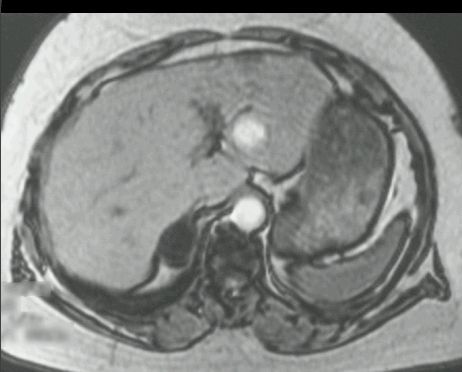

GRUCZOLAK NADNERCZA

MR